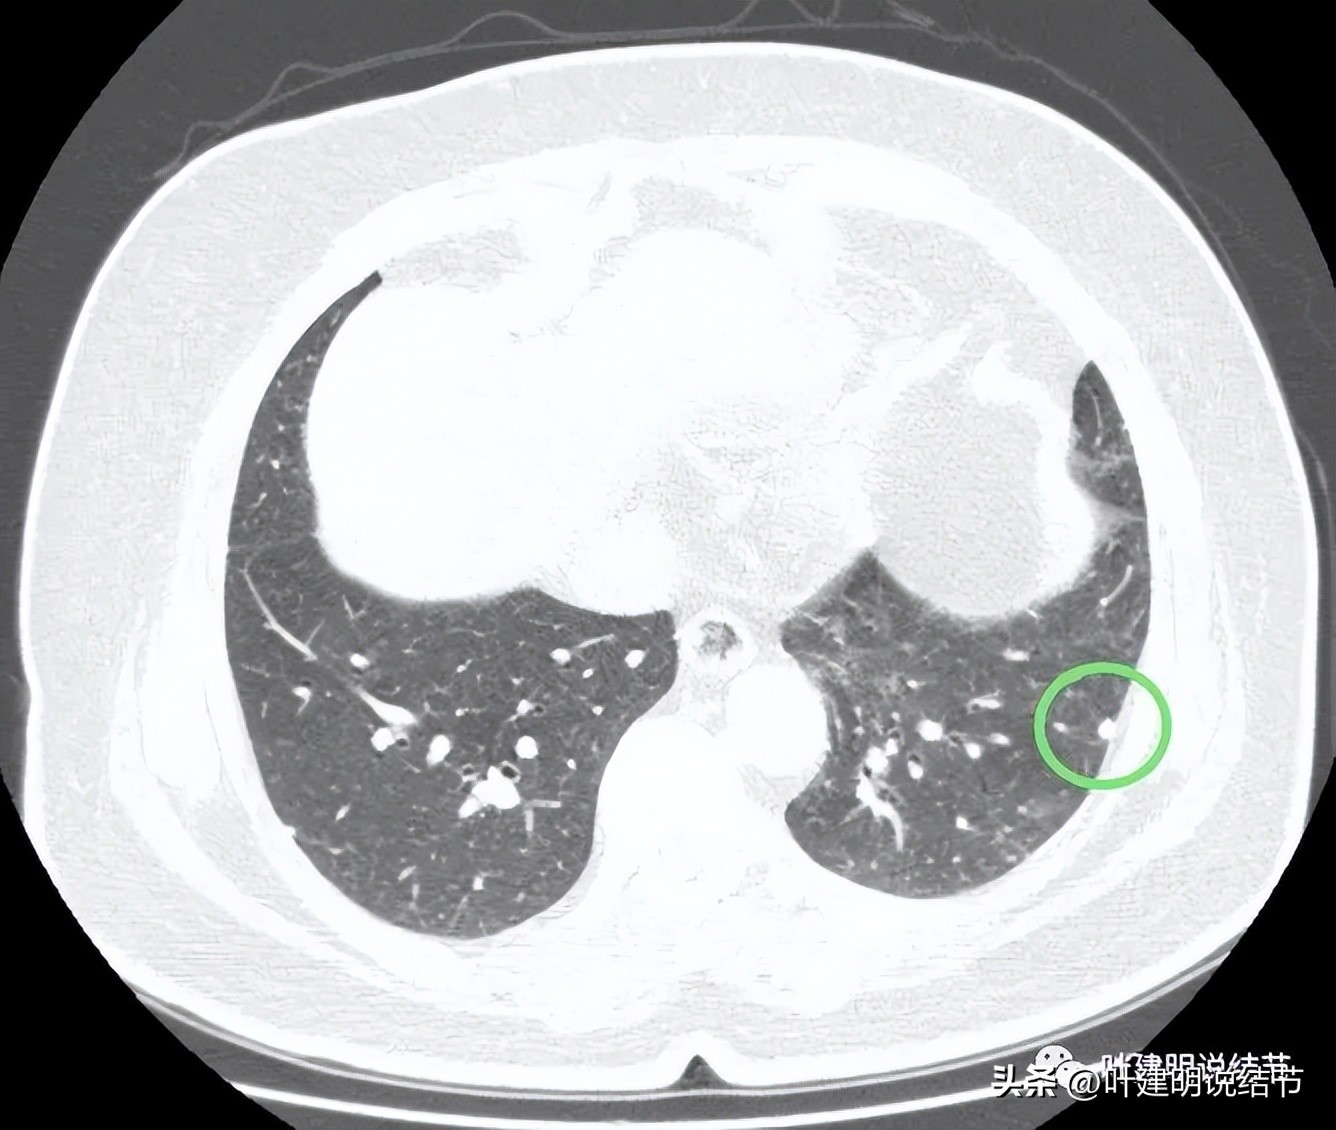

病灶3:左下叶微小实性结节,边光滑,圆形,密度高,考虑良性可能性大;